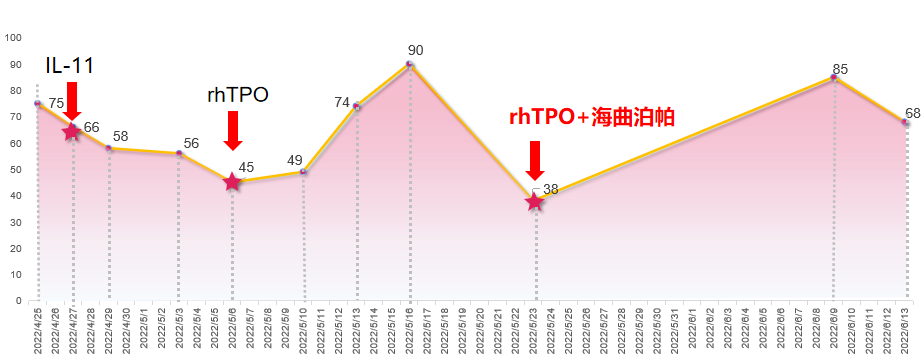

患者于2022-4-22开始第6周期化疗联合免疫治疗,并同步进行放疗。2022-4-25出现II度骨髓抑制,血小板75×109/L,予重组人白介素-11(rhIL-11)治疗10天,但血小板持续下降至45×109/L,且出现下肢水肿,遂改为重组人血小板生成素(rhTPO)治疗7天,血小板升高至90×109/L。在持续的抗肿瘤治疗下,患者再次出现CTIT(血小板38×109/L),给予rhTPO 15000IU皮下注射3天,联合海曲泊帕5mg 口服治疗10天,血小板维持稳定。

患者第1周期化疗结束后再次出现II度骨髓抑制,血小板降至63×109/L,予海曲泊帕7.5mg/天进行院外治疗,11天后患者返院,复查血常规升至120×109/L,顺利完成第2周期化疗。

本例患者确诊食管胃结合部腺癌Ⅳ期,HER-2阴性,基于指南推荐以及循证证据,给予化疗联合免疫治疗一线治疗7周期,复查CT提示疾病进展,故联合放疗。在三种抗肿瘤治疗方式的联合作用下,患者出现CTIT,血小板下降至75×109/L。给予rhIL-11治疗10天疗效欠佳,血小板持续下降,且出现下肢水肿不良反应,改为rhTPO治疗7天后血小板降低得以改善。然而随着治疗周期的增加,患者在下一周期出现了更为严重的血小板减少症,血小板降至38×109/L,遂予以新一代血小板生成素受体激动剂(TPO-RA)海曲泊帕联合rhTPO治疗,血小板快速回升,保证患者按时按量的完成抗肿瘤治疗。此后患者复查CT再次提示疾病进展,重新评估病情后予白蛋白紫杉醇单药化疗,化疗过程中再次出现血小板下降。考虑rhTPO针剂注射治疗需住院或频繁返院,增加相关治疗成本,因此给予患者海曲泊帕7.5mg/天行院外治疗,有效且便捷地提升血小板,使患者顺利完成后续治疗。